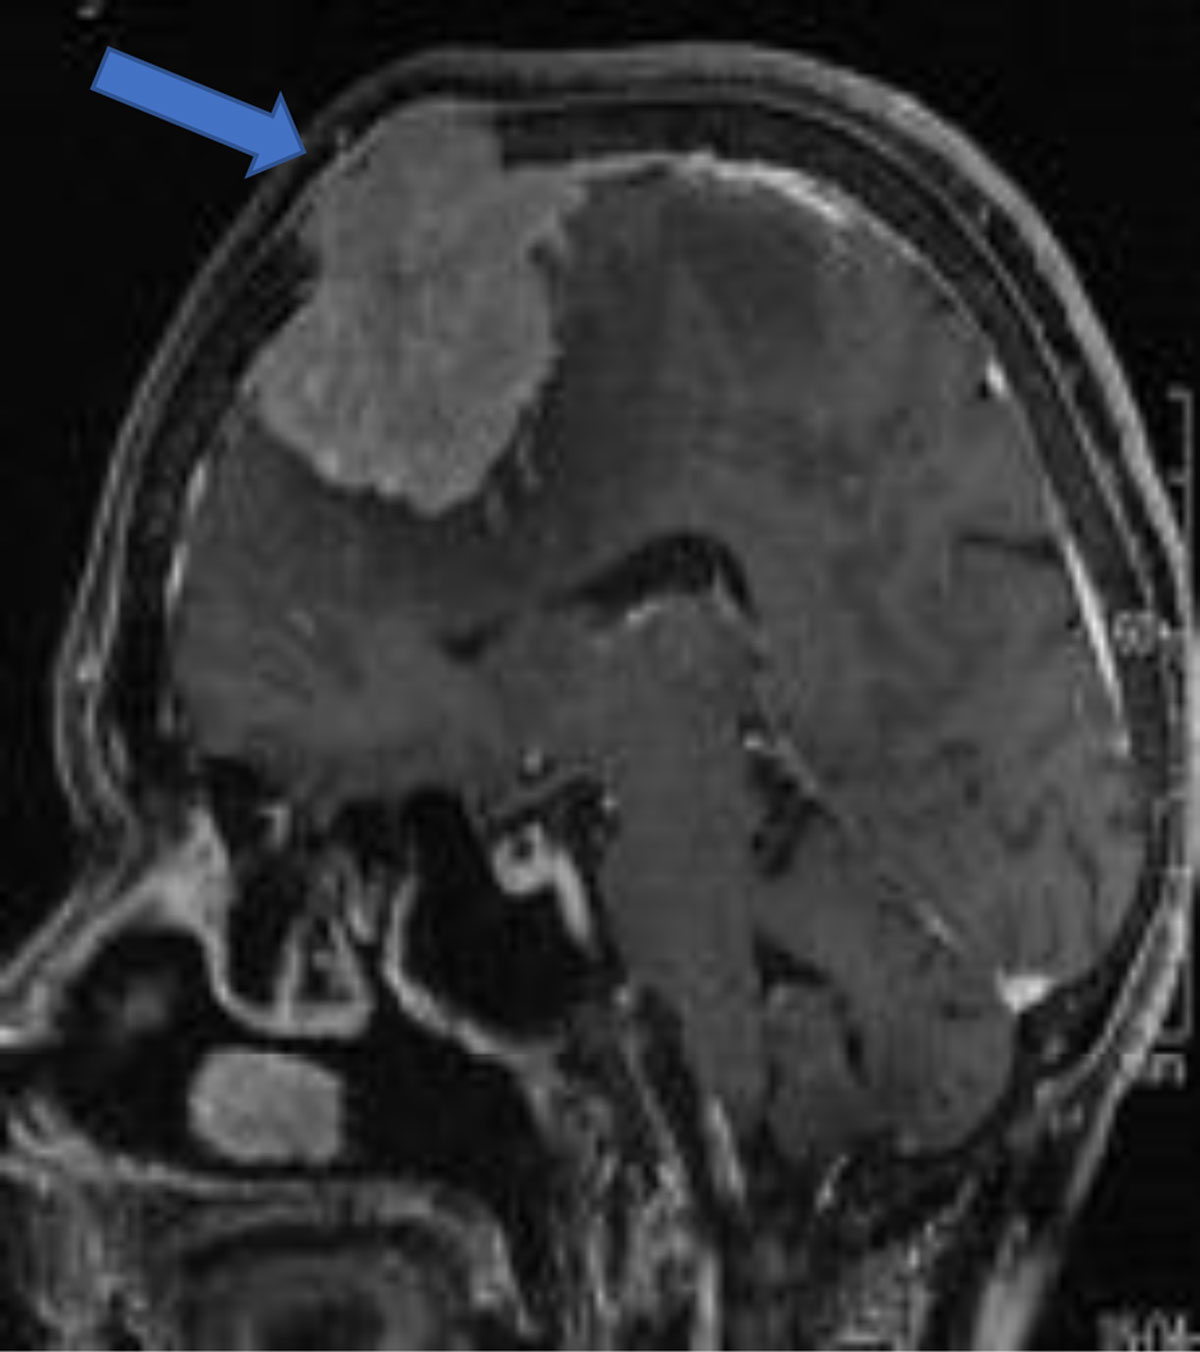

Figure 10

Sagittal post-contrast convexity meningioma with osseous invasion (arrow).